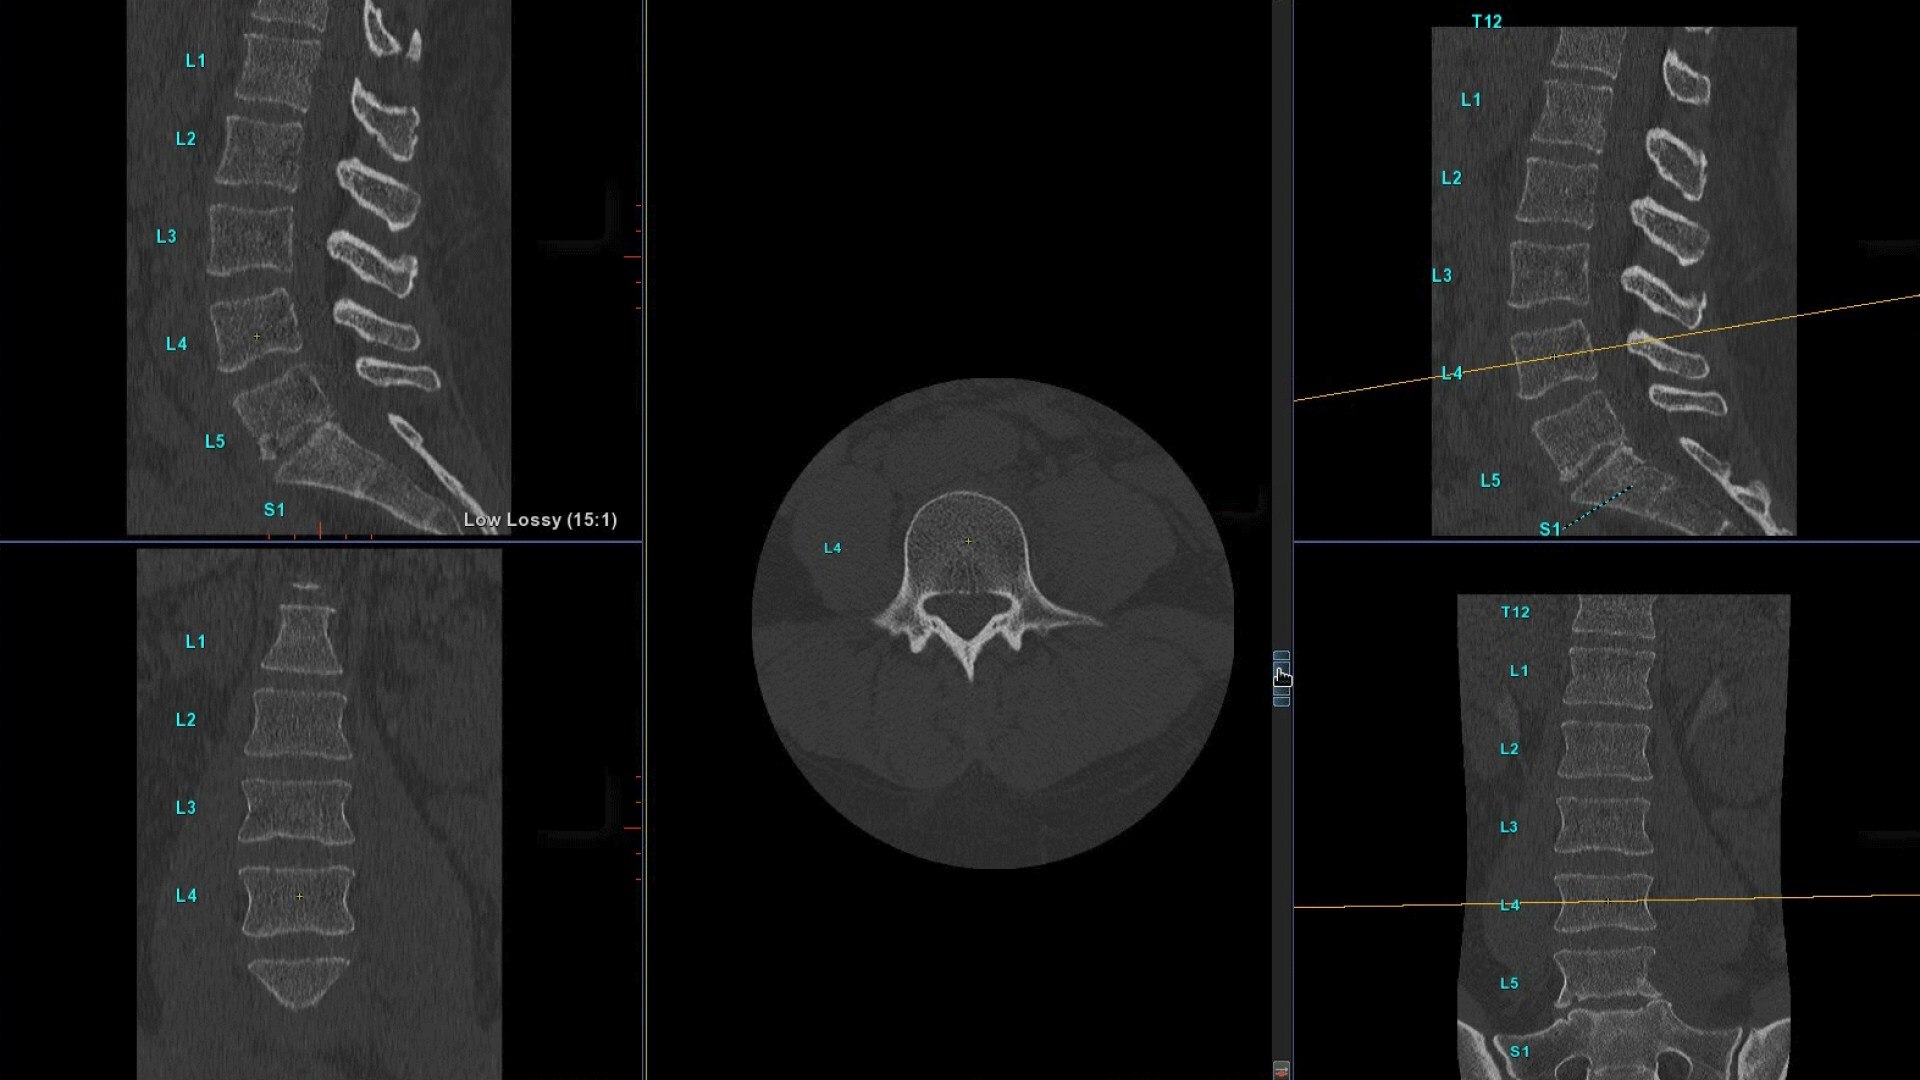

Bone VCAR

Spine assessment with deep-learning based CT application.

• Automated generation of a 3D trace to generate oblique and straightened reformat views

• Automated generation of oblique views perpendicular to vertebral bodies and disc spaces

• Easily edit the centerline to ensure accurate placement in the most challenging cases

• Works on full spine acquisitions as well as limited acquisitions containing segments of the spine